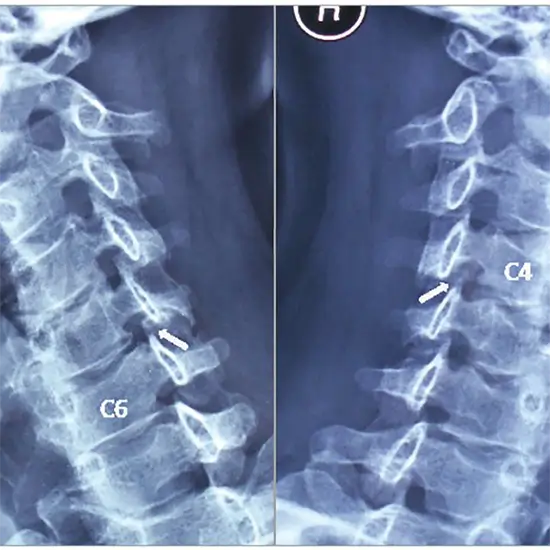

X-Ray of the Cervical Spine Both Oblique Views examine the neck region's first seven vertebrae (C1-C7) of the spinal column (backbone).